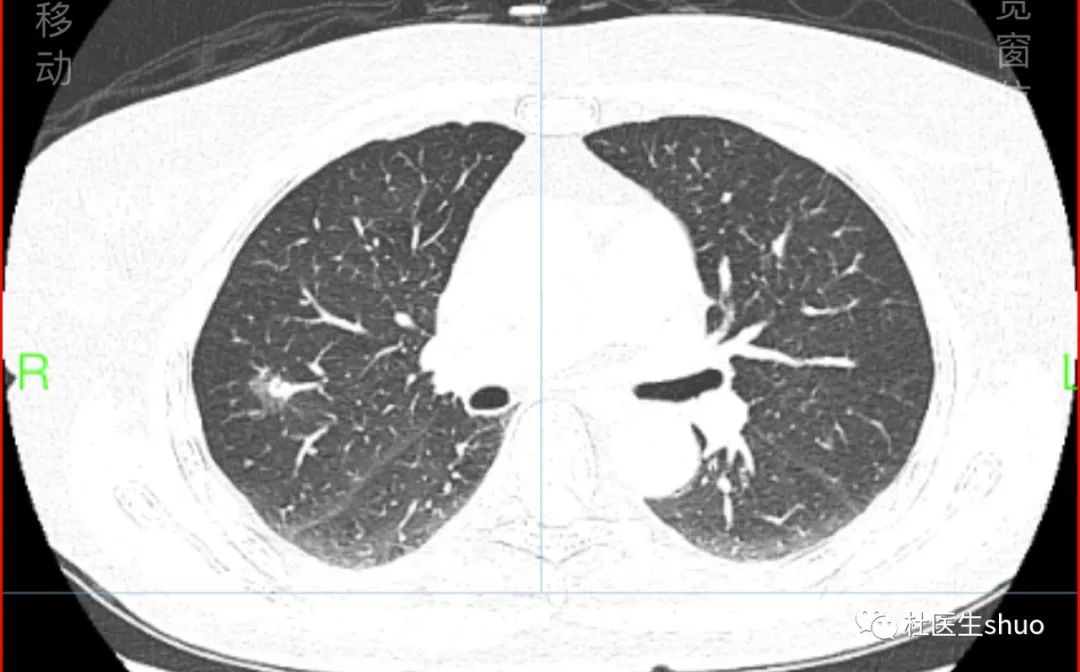

65岁女性右肺上叶部分实性结节